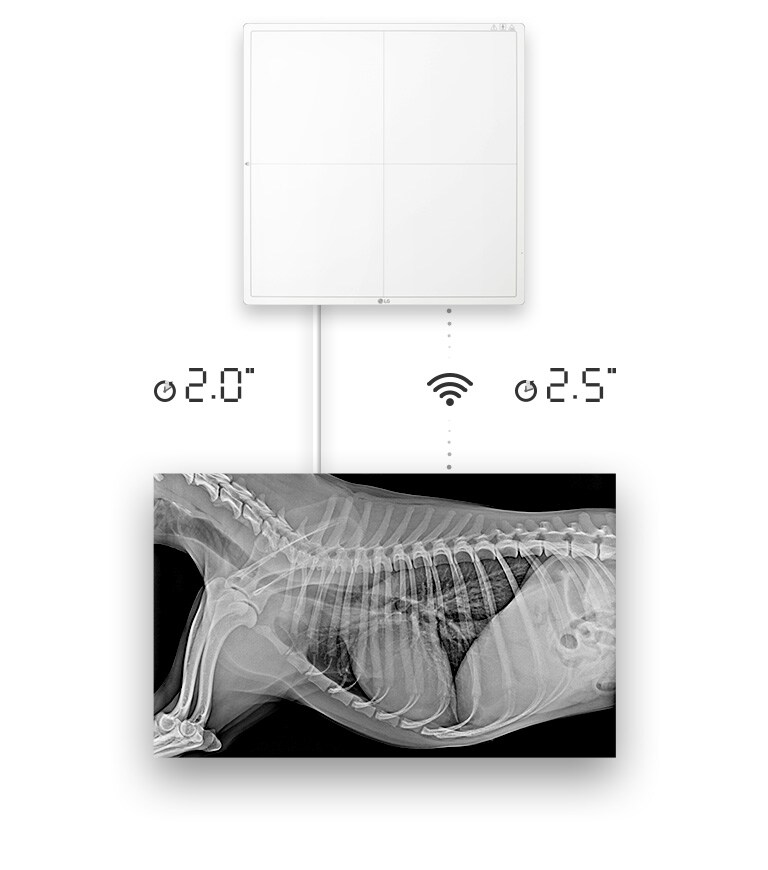

Amélioration de l'efficacité du travail

Disponibilité rapide des images

Disponibilité de l’image brute en 2 secondes avec une connexion filaire, ou 2,5 secondes avec une connexion sans fil

*Le mode Point d’accès est disponible lorsqu’il est associé au logiciel du poste d’acquisition LG.

TRANSFERT IMAGE COMPLÈTE(TYP.)

Transfert Image Complète (Typ.)

2 sec (Avec Fil) / 2.5 sec (Sans Fil)